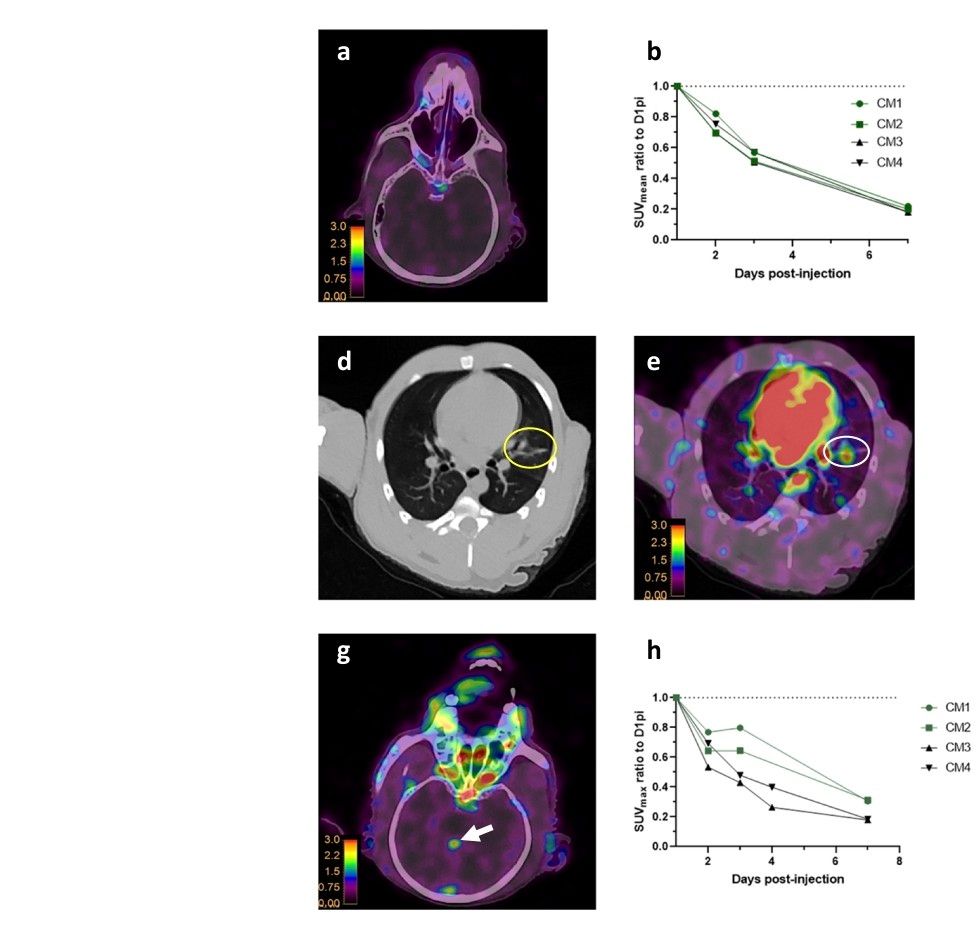

SARS-COV-2 Invades Lungs, Brain, Nasal Passages, Airways, and Kidneys: Imaging Tracks COVID-19's Hidden Locations 3 months after infection https://t.co/vfuxc952wY